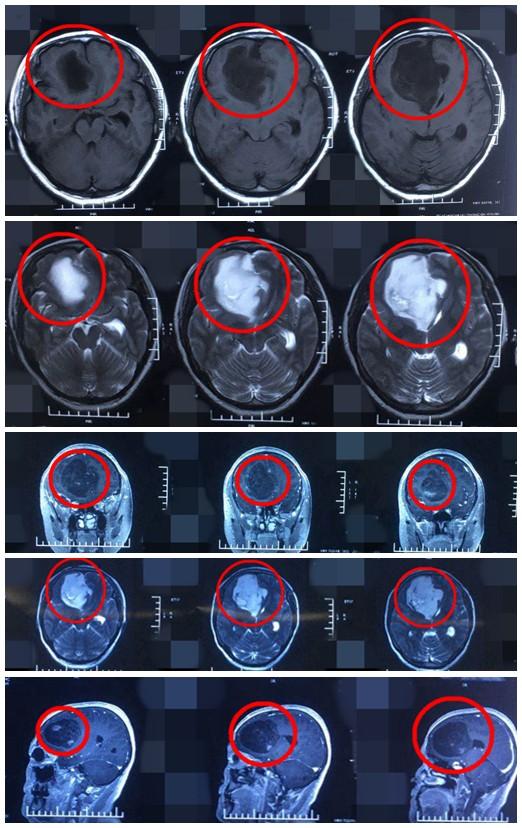

右侧肢体无力检查后竟是恶性脑肿瘤